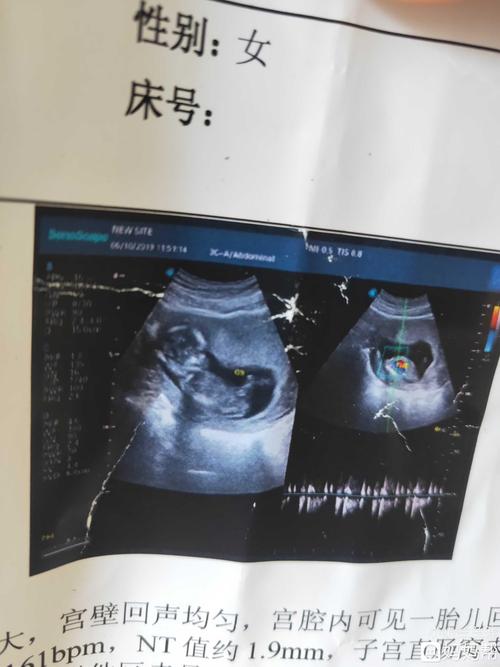

三个月的b超单,能看出男孩女孩吗

怀孕11周做的彩超,各位能不能看出是男宝还是女宝?

3个月nt检查已过,,请各位宝妈看看是男

怀孕三个月看不出男孩女孩吗?昨天刚做的闭超.成熟都'i了,还看不见吗?

怀孕三个月胎儿彩超

三个月胎儿图彩超图片